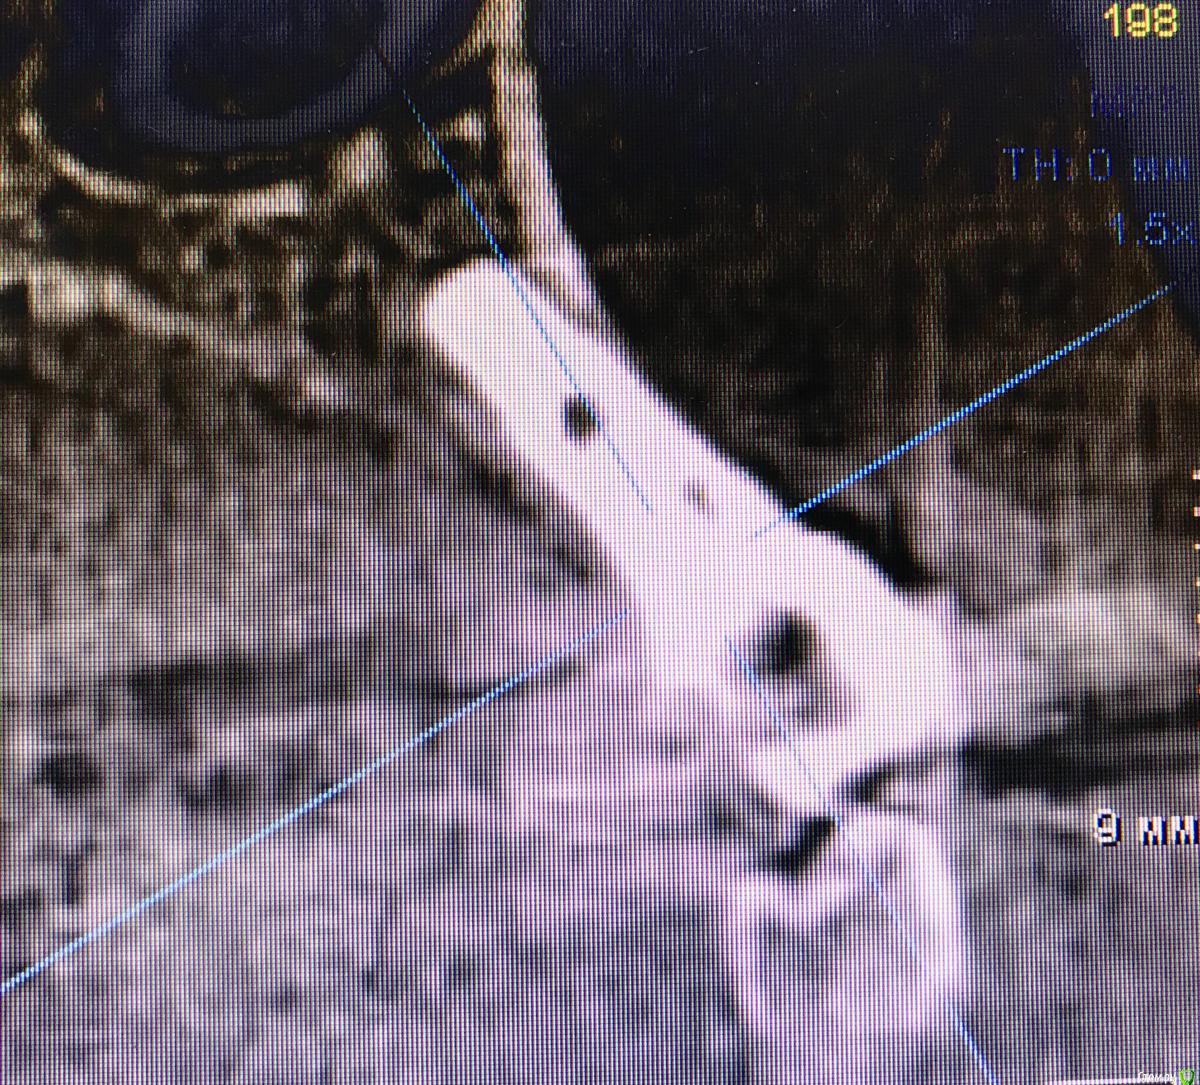

DenisV Опубликовано 21 марта, 2018 Поделиться Опубликовано 21 марта, 2018 Уважаемые коллеги планируется удаление и установка имплантата 3.8 10 dentium можно ли будет обойтись без костной и тканевой аугментации? Ссылка на комментарий

DenisV Опубликовано 21 марта, 2018 Автор Поделиться Опубликовано 21 марта, 2018 Уважаемые коллеги планируется удаление и установка имплантата 3.8 10 dentium можно ли будет обойтись без костной и тканевой аугментации? Ссылка на комментарий

колесников Опубликовано 21 марта, 2018 Поделиться Опубликовано 21 марта, 2018 Можно,но не нужно. Размеры оптимальные. Немедленная нагрузка показана. Стремитесь к винтовой фиксации,длинный Имплант в этом случае будет сложно расположить. Удалять атравматично,лоскут не откидывать, Сст вестибулярно 1 Ссылка на комментарий

Irouil Опубликовано 21 марта, 2018 Поделиться Опубликовано 21 марта, 2018 (изменено) Почему тут 3.6*12 не войдёт? По моему на винтовую выводится. 10мм тоже норм, но для немедленной нагрузки 2мм лишними будут? Изменено 21 марта, 2018 пользователем Irouil 1 Ссылка на комментарий

колесников Опубликовано 21 марта, 2018 Поделиться Опубликовано 21 марта, 2018 (изменено) Чтобы отвертка не уперлась в режущий край,ставить лучше более вертикально,Апекс в этом случае будет близко к вестибулярной компактной пластинке ,после нагрузки может быть окончатся резорбция. Мне кажется, 10 мм с заглублением, самое то. Изменено 21 марта, 2018 пользователем колесников 1 Ссылка на комментарий